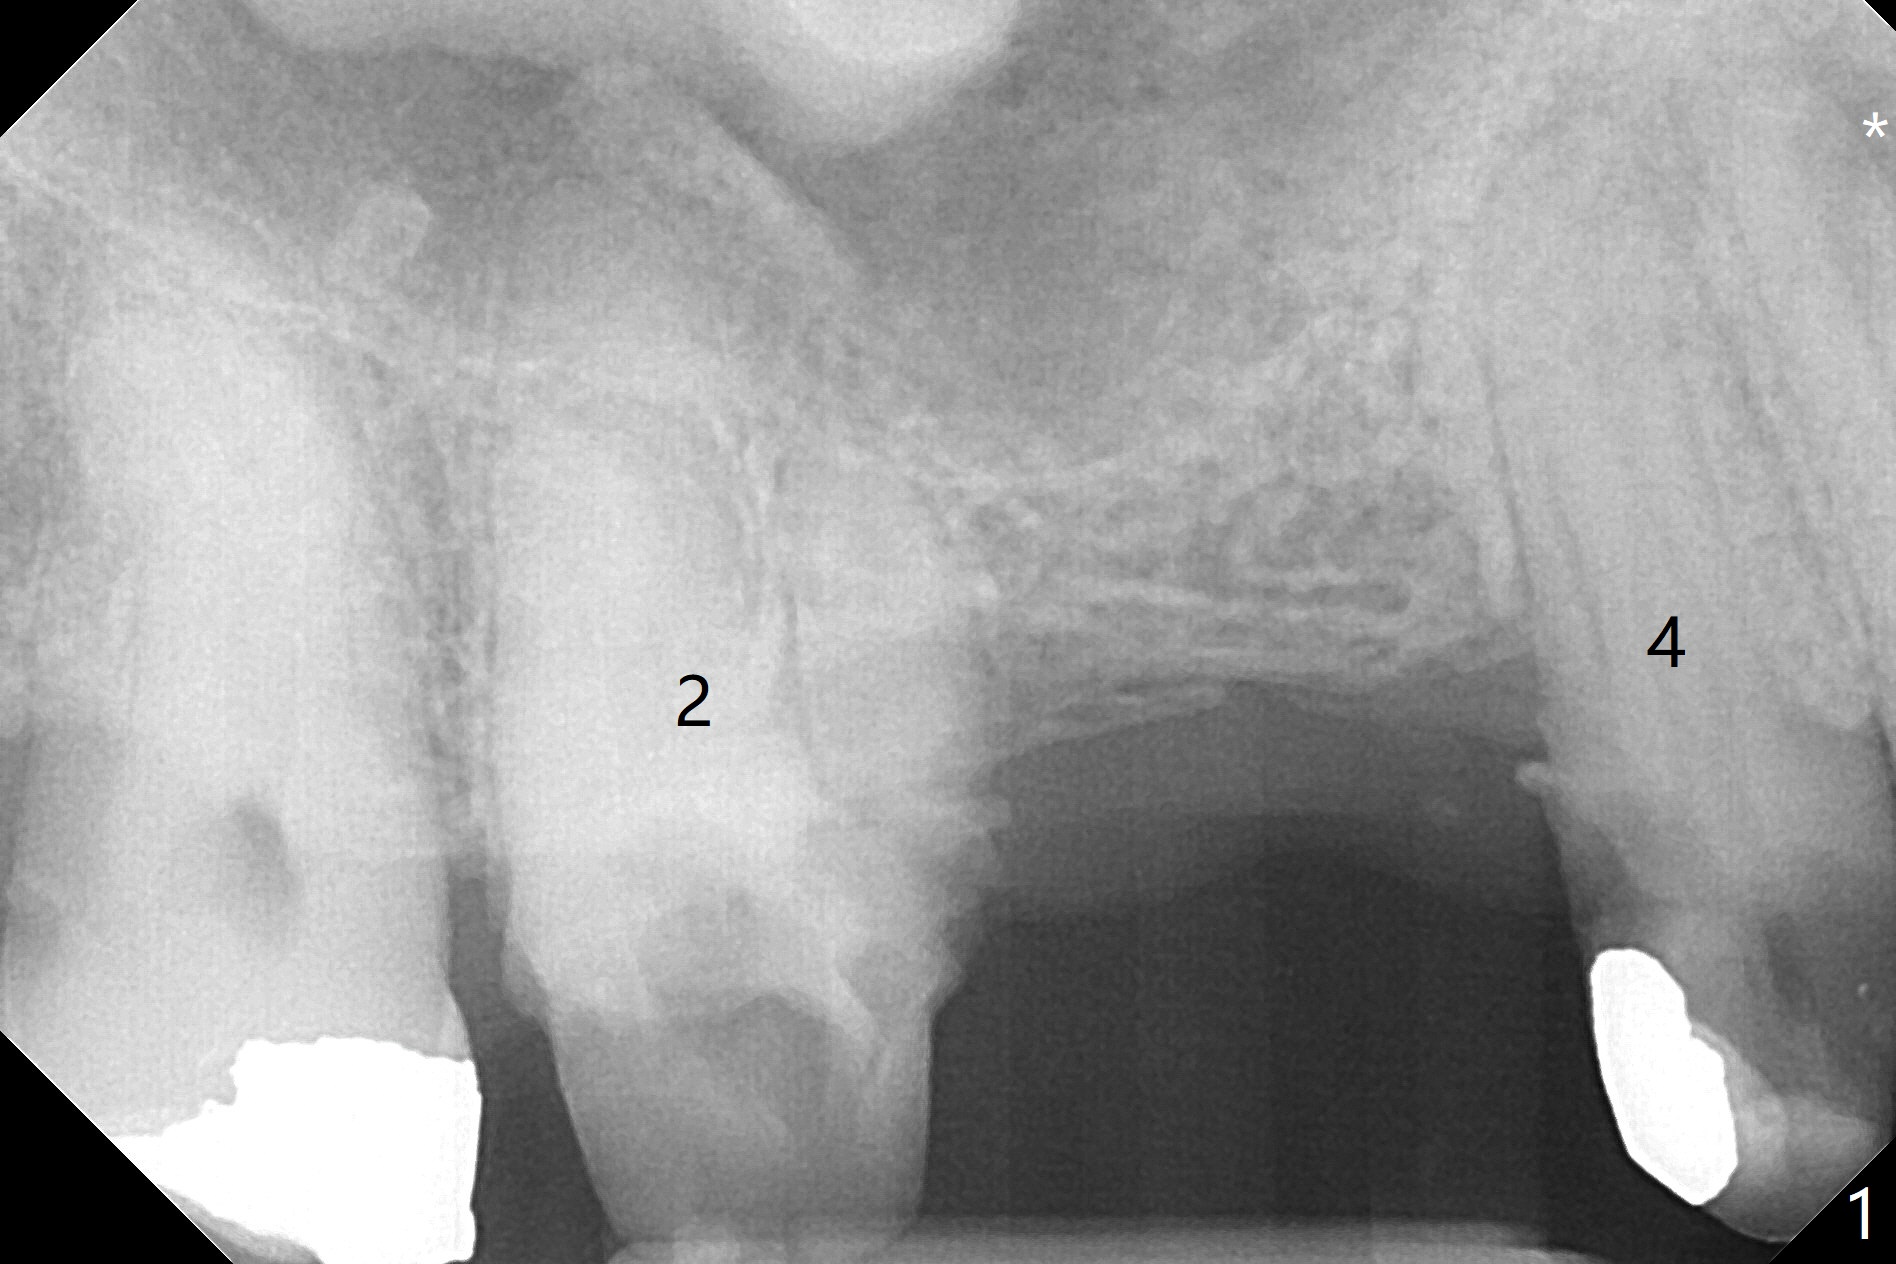

A 64-year-old man requests implant restoration after the upper FPD dislodges (Fig.1). The measurement of the septal height at #2 by PA (Fig.2) is not as precise as CBCT (Fig.11, taken 4 years earlier). There appears to be 2.8 mm bone apical to the tooth #4 (Fig.2); in contrast, the bone is more or less buccal and palatal to the root apex shown by CT (Fig.5). Furthermore CT more clearly shows apical lesions of the tooth #5 (Fig.3,4) than PA (Fig.2). In addition to pulpal test, RCT should be done for #5 prior to implant placement at #4.